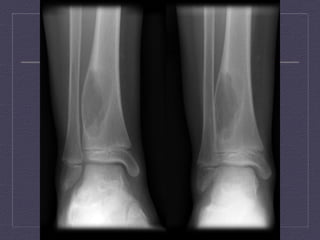

AP  and  lateral  views  of  the  right  hip  demonstra:ng  a  ly:c  lesion   with  peripheral  sclerosis  of  the  right  proximal  femur